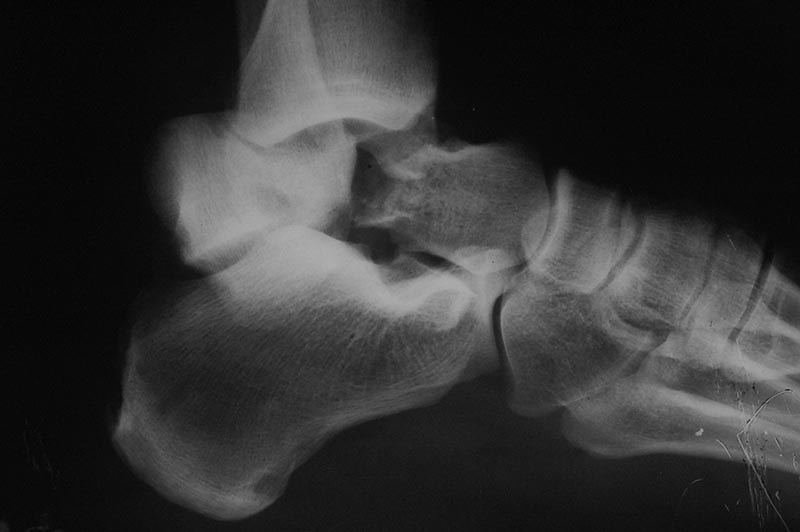

Извините "корявые" руки травматолога и нет не дружат:). Выкладываю первичный снимок. Если можно более конкретно методики артродезов. Делали все кроме стержня. И основной вопрос как определить границу жизнеспособной таранной кости???

Вероятнее всего, речь изначально шла о не устраненном во время операции вывихе проксимального фрагмента таранной кости.

Во вложении похожий случай, оперированный 10 дней назад (с послеоперационными снимками). Для сравнения стрелками на двух рентгенограммах показан нависающий над пяточной костью вывихнутый фрагмент таранной кости. На компьютерной томограмме видно гораздо лучше. Так что о живом подтаранном суставе при сохраняющемся подвывихе говорить не приходится. Кстати, остеотомия внутренней лодыжки в такой ситуации - нормальный этап доступа, который должен планироваться до операции, а не быть следствием "тяжелой репозиции". Сейчас же, судя по плотности проксимального фрагмента, нужно исключать асептический некроз таранной кости и ее несращение. От этого будет зависеть тактика. Без КТ не обойтись. Во всяком случае, артродез голеностопного сустава при несросшейся разрушающейся таранной кости точно не будет правильным решением.